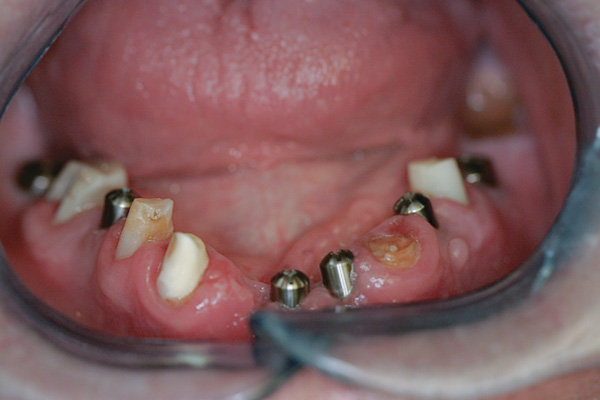

Background: In this case, the patient had a failing mandibular and maxillary dentition due to caries secondary to radiation-induced xerostomia. The patient had had a radical neck dissection to remove a squamous cell carcinoma of the throat 9 years prior to his prosthodontic consultation with the authors. The patient reported a history of radiation therapy following surgery, but did not have a shielding stent. A staged approach was used so as to avoid removable prosthetics on his severely dry soft tissues. He chose to treat his mandibular issues first. Figure 9 shows healing abutments next to the temporarily retained natural teeth, and Figure 10 shows the first-stage custom abutments inserted with relatively good gingival contour and no recession. Recession was clearly seen around all first-stage abutments following adjacent extractions and second-stage implant placement (Figure 11).

Figure 11 Recession evident around first-stage abutments following adjacent extractions and second-stage implant placement.

Figure 11